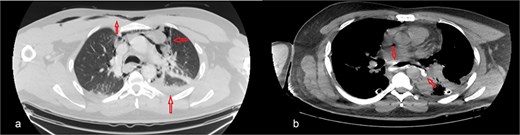

The patient was diagnosed with EP. Gastroscopy showed a 2 cm tear at 27–28 cm from the incisors and erosive esophagitis at the gastroesophageal junction (GEJ). Chest CT confirmed pneumomediastinum, subcutaneous emphysema, pleural effusion, and aspiration pneumonia (Fig. 2). The patient was transferred to the SICU for intensive monitoring. On Day 2, a right thoracotomy was performed, revealing a linear esophageal tear, food collection (mainly red meat), and a 1 cm through-and-through perforation. The procedure included debridement, defect repair with pleural patch reinforcement, and chest tube placement. The patient was monitored postoperatively in the SICU. On Day 4, the patient was extubated, and gastroscopy on Day 10 confirmed healing. An esophageal stent was placed on Day 11, with gradual clinical improvement and tolerance of oral fluids. Chest tubes were transitioned to water-seal drainage. Recurrent stent migrations occurred on Days 15, 17, and 19, requiring repositioning and eventual removal. On Day 20, bronchoscopy identified a broncho-esophageal fistula, and chest CT showed reduced leakage (Fig. 3). The patient was kept nothing by mouth (NPO) for further healing.

Chest CT scan: (a) with IV contrast, extensive pneumomediastinum as well as extensive cervical and anterior chest subcutaneous surgical emphysema with mild bilateral pleural effusion. (b) IV and oral contrast: Evidence contrast leakage arising from the left posterolateral aspect of mid esophagus associated with mild left loculated pleural effusion and mild pneumomediastinum.